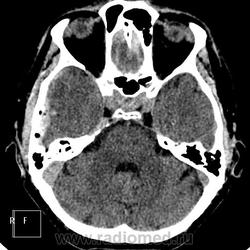

Линейный перелом теменной (доходит до лямбдовидного шва) и чешуи височной кости справа. Поднадкостничное кровоизлияние (между костью тв. мозговой оболочкой (субдуральное?)). Пневматизация пирамиды правой височной кости понижена (это могло быть и до травмы). Вроде бы и в мозговом веществе локально какие-то неопределённые изменения (фаназия?)

Линейный перелом теменной кости справа, субдуральная гематома в теменновисочной области справа всочетаниис контузионными очагами 1-2 типа в височной доле на этой стороне и в лобной с двух сторон больше на основании .Передний рог бокового желудочка справа компремирован. Базальные цистерны без деформации.

Всё так, только я написала смешанную гематому и перелом теменной и височной кости. Плюс САК сильвиевой щели (здесь сканов маловато, но при посрезовом просмотре четко определяется). Консервативное лечение пациента.

Да, как мне видится, в височной эпидуральная, ближе к теменной - субдуральная. Понимаю, что в височных субдуралки могут иметь форму линзы и походить на эпидуральные. В-общем, не стала бы категорически утверждать, что права))

Согласен так называемая "двухэтажная" гематома.